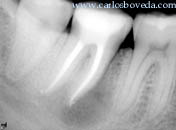

Radiográficamente se aprecia la condición de la zona. Notese lo extenso del área radiolúcida periapical a la raíz mesial.

Una radiovisiografía del área permite comparar imágenes.

Imagen radiográfica del recorrido de este tercer conducto mesial.